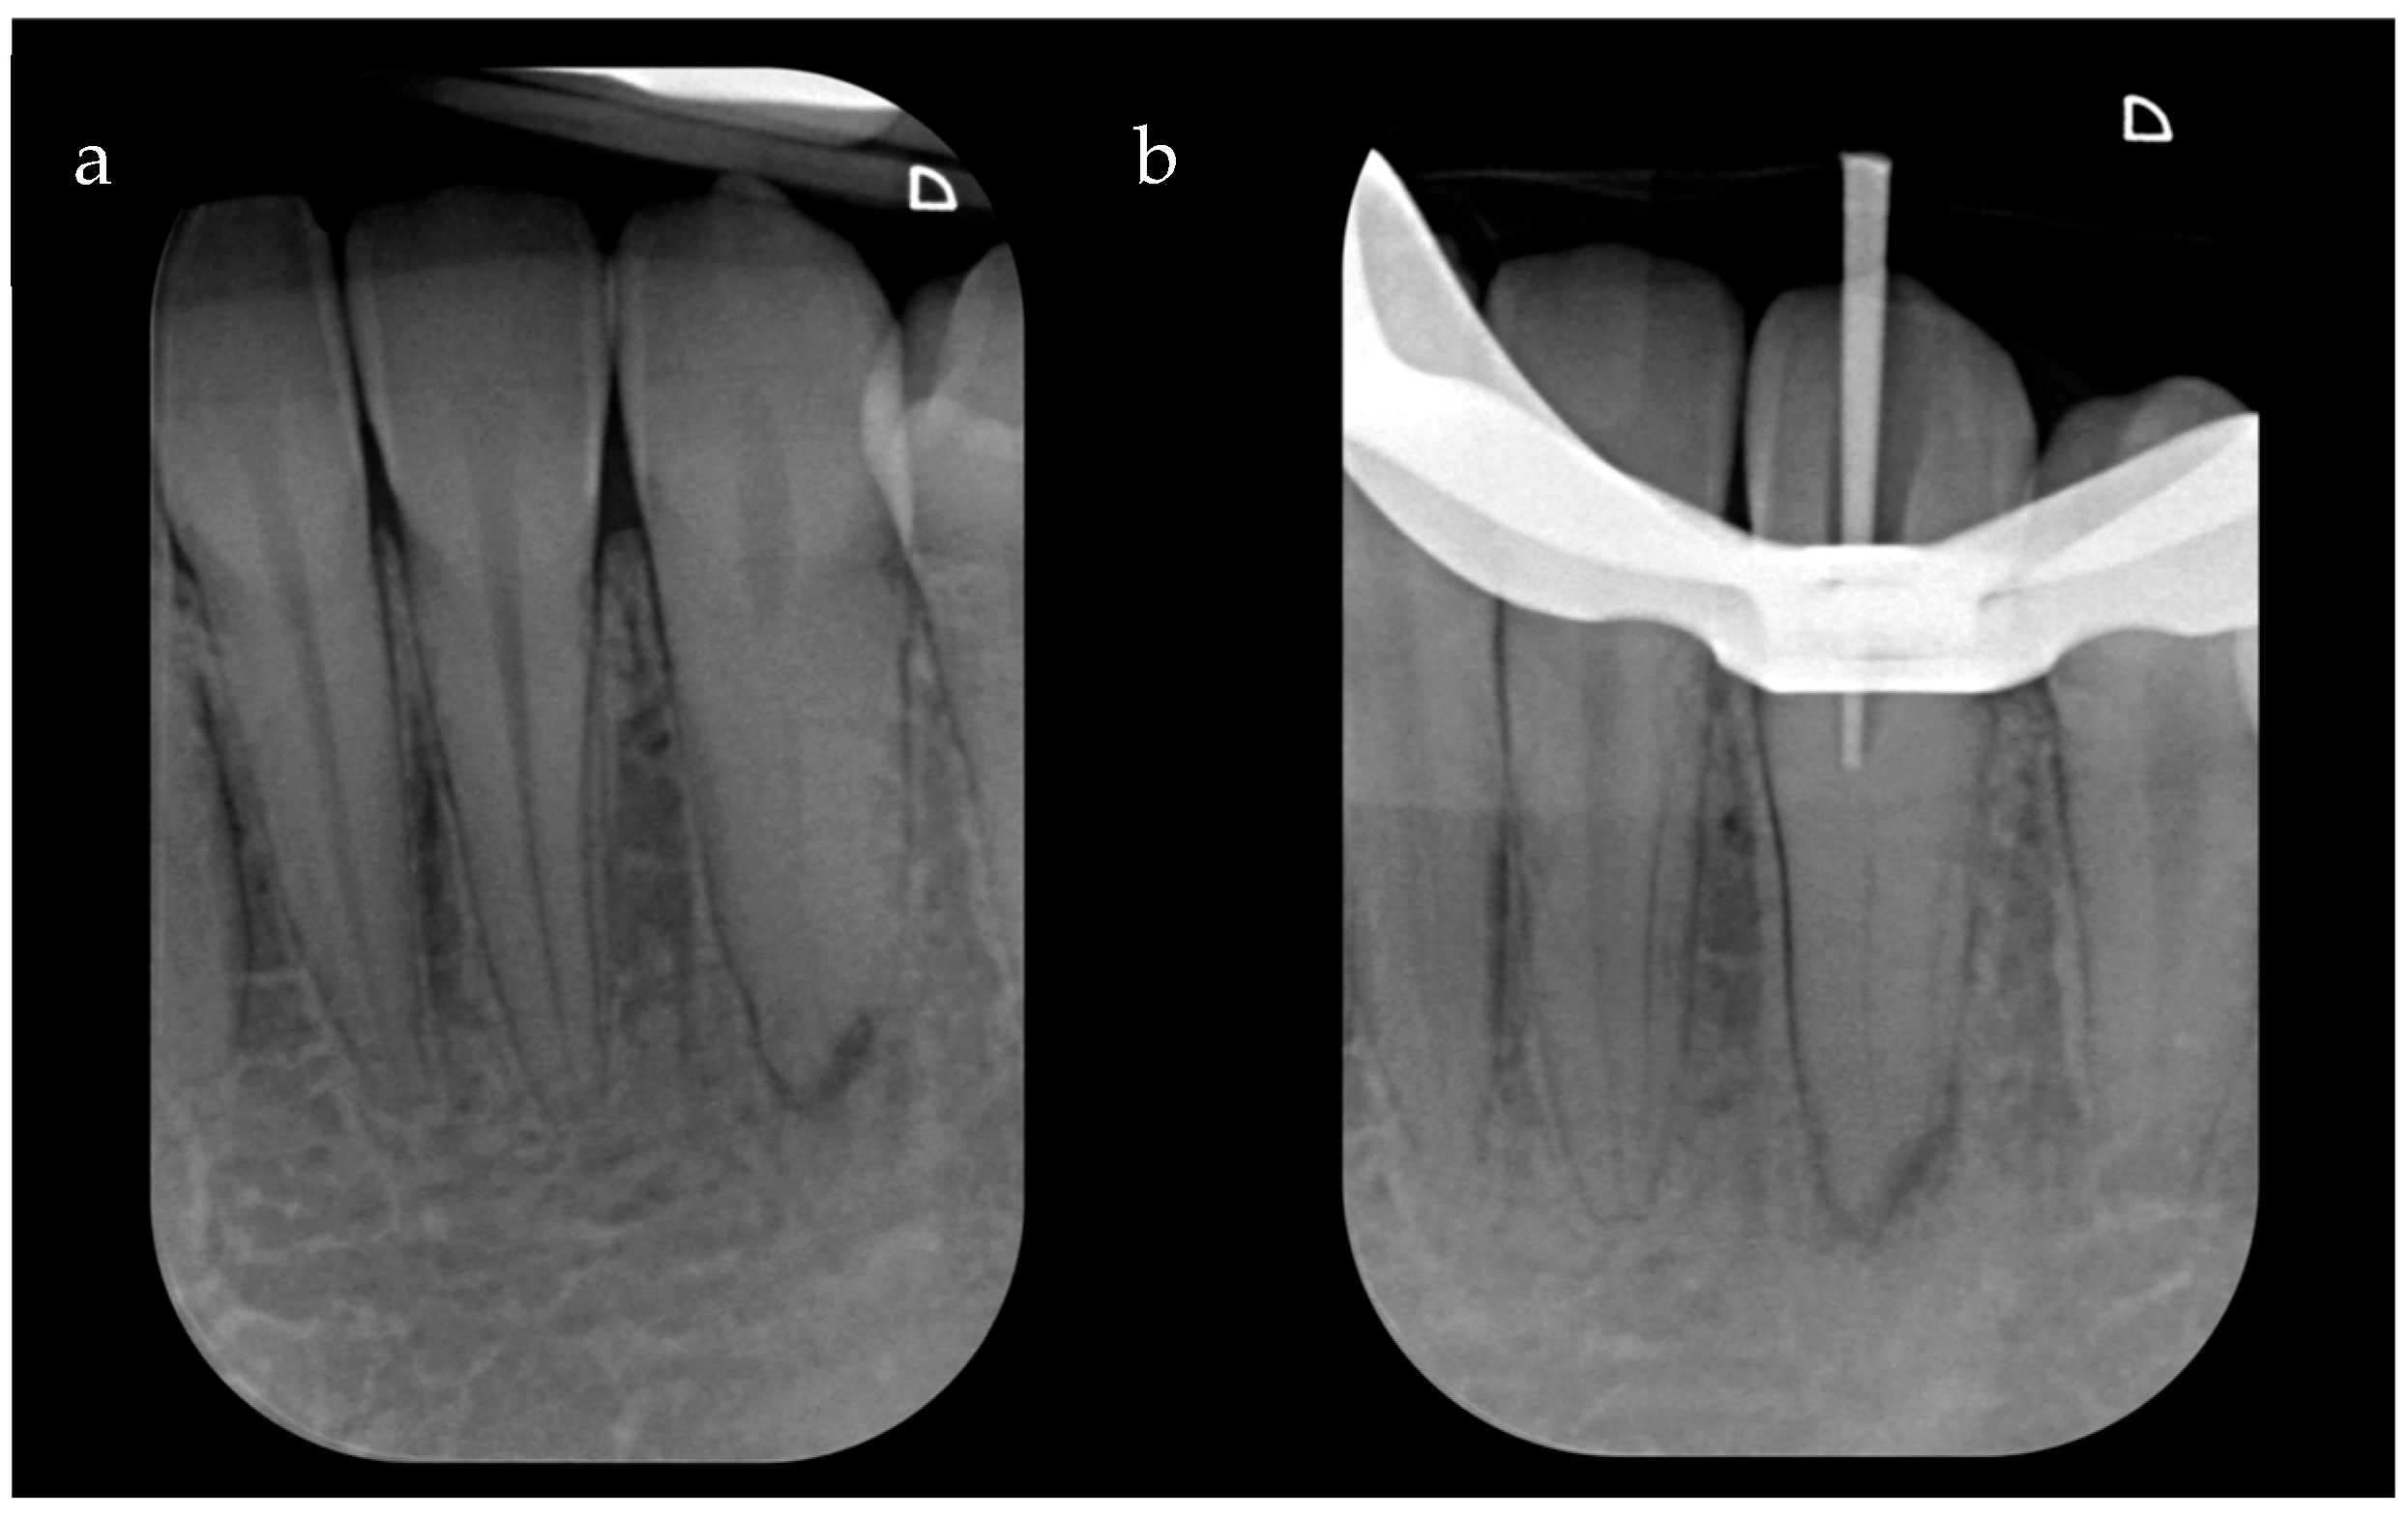

An initial periapical X-ray using the long-cone parallel technique revealed a clearly identifiable root canal space and periapical radiolucency of PAI 3 (changes in bone structure with light mineral loss) (Figure 1a). Tooth 3.3 was diagnosed as necrotic pulp with symptomatic apical periodontitis and was planned for nonsurgical root canal therapy. Considering the pre-operative, X-ray which notably showcased the root canal, a pre-operative CBCT was deemed unnecessary, and it was decided to proceed with the traditional treatment consisting of the freehand ultrasonic technique and a dental operating microscope.

After local anesthesia (Articaine Septanest with adrenaline 1:200,000; Septodont, Saint-Maur-des-Fosses, France), and rubber dam isolation, the access cavity was prepared under a dental operating microscope (Leica M500, Leica Microsystems, Wetzlar, Germany) with a diamond access bur (Dentsply Sirona 851012 FG safe end bur, Dentsply Sirona, Charlotte, NC, USA). Afterwards, an ultrasonic handpiece (Satelec, Acteon, Merignac, France) with an Endodontic Treatment Exploration Ball Diamond Tip ultrasonic tip (Satelec P5® Piezo, Acteon, Merignac, France) was used in endo mode. However, this initial attempt to negotiate the canal led to a small deviation that hindered further progress. Indeed, an intra-operative X-ray with a gutta-percha cone was performed, which showcased a small deviation that was hindering further progress (Figure 1b). Given the expressed desire of the patient to preserve the natural element, a different treatment strategy was proposed.

Figure 1. (a) Pre-operative X-ray; small periapical radiolucent area. (b) Intra-operative X-ray with a gutta-percha cone to evaluate the trajectory of the initial preparation carried out with ultrasonic inserts. It is impossible to reach the canal despite using the operating microscope, and the cone shows that one is proceeding in the wrong direction.